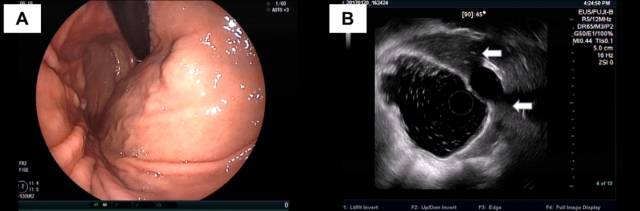

下面患者在外院胃镜和CT(图 A-B)均考虑胃底粘膜下肿瘤,拟双镜联合切除。

术前来我院完善超声内镜检查提示肝左叶近膈顶血管瘤(图A-B)

图A:环扫EUS提示肝脏近膈顶类圆形血管瘤(白色箭头);图B:线阵EUS见病灶上方的固有肌层完整(白色箭头)